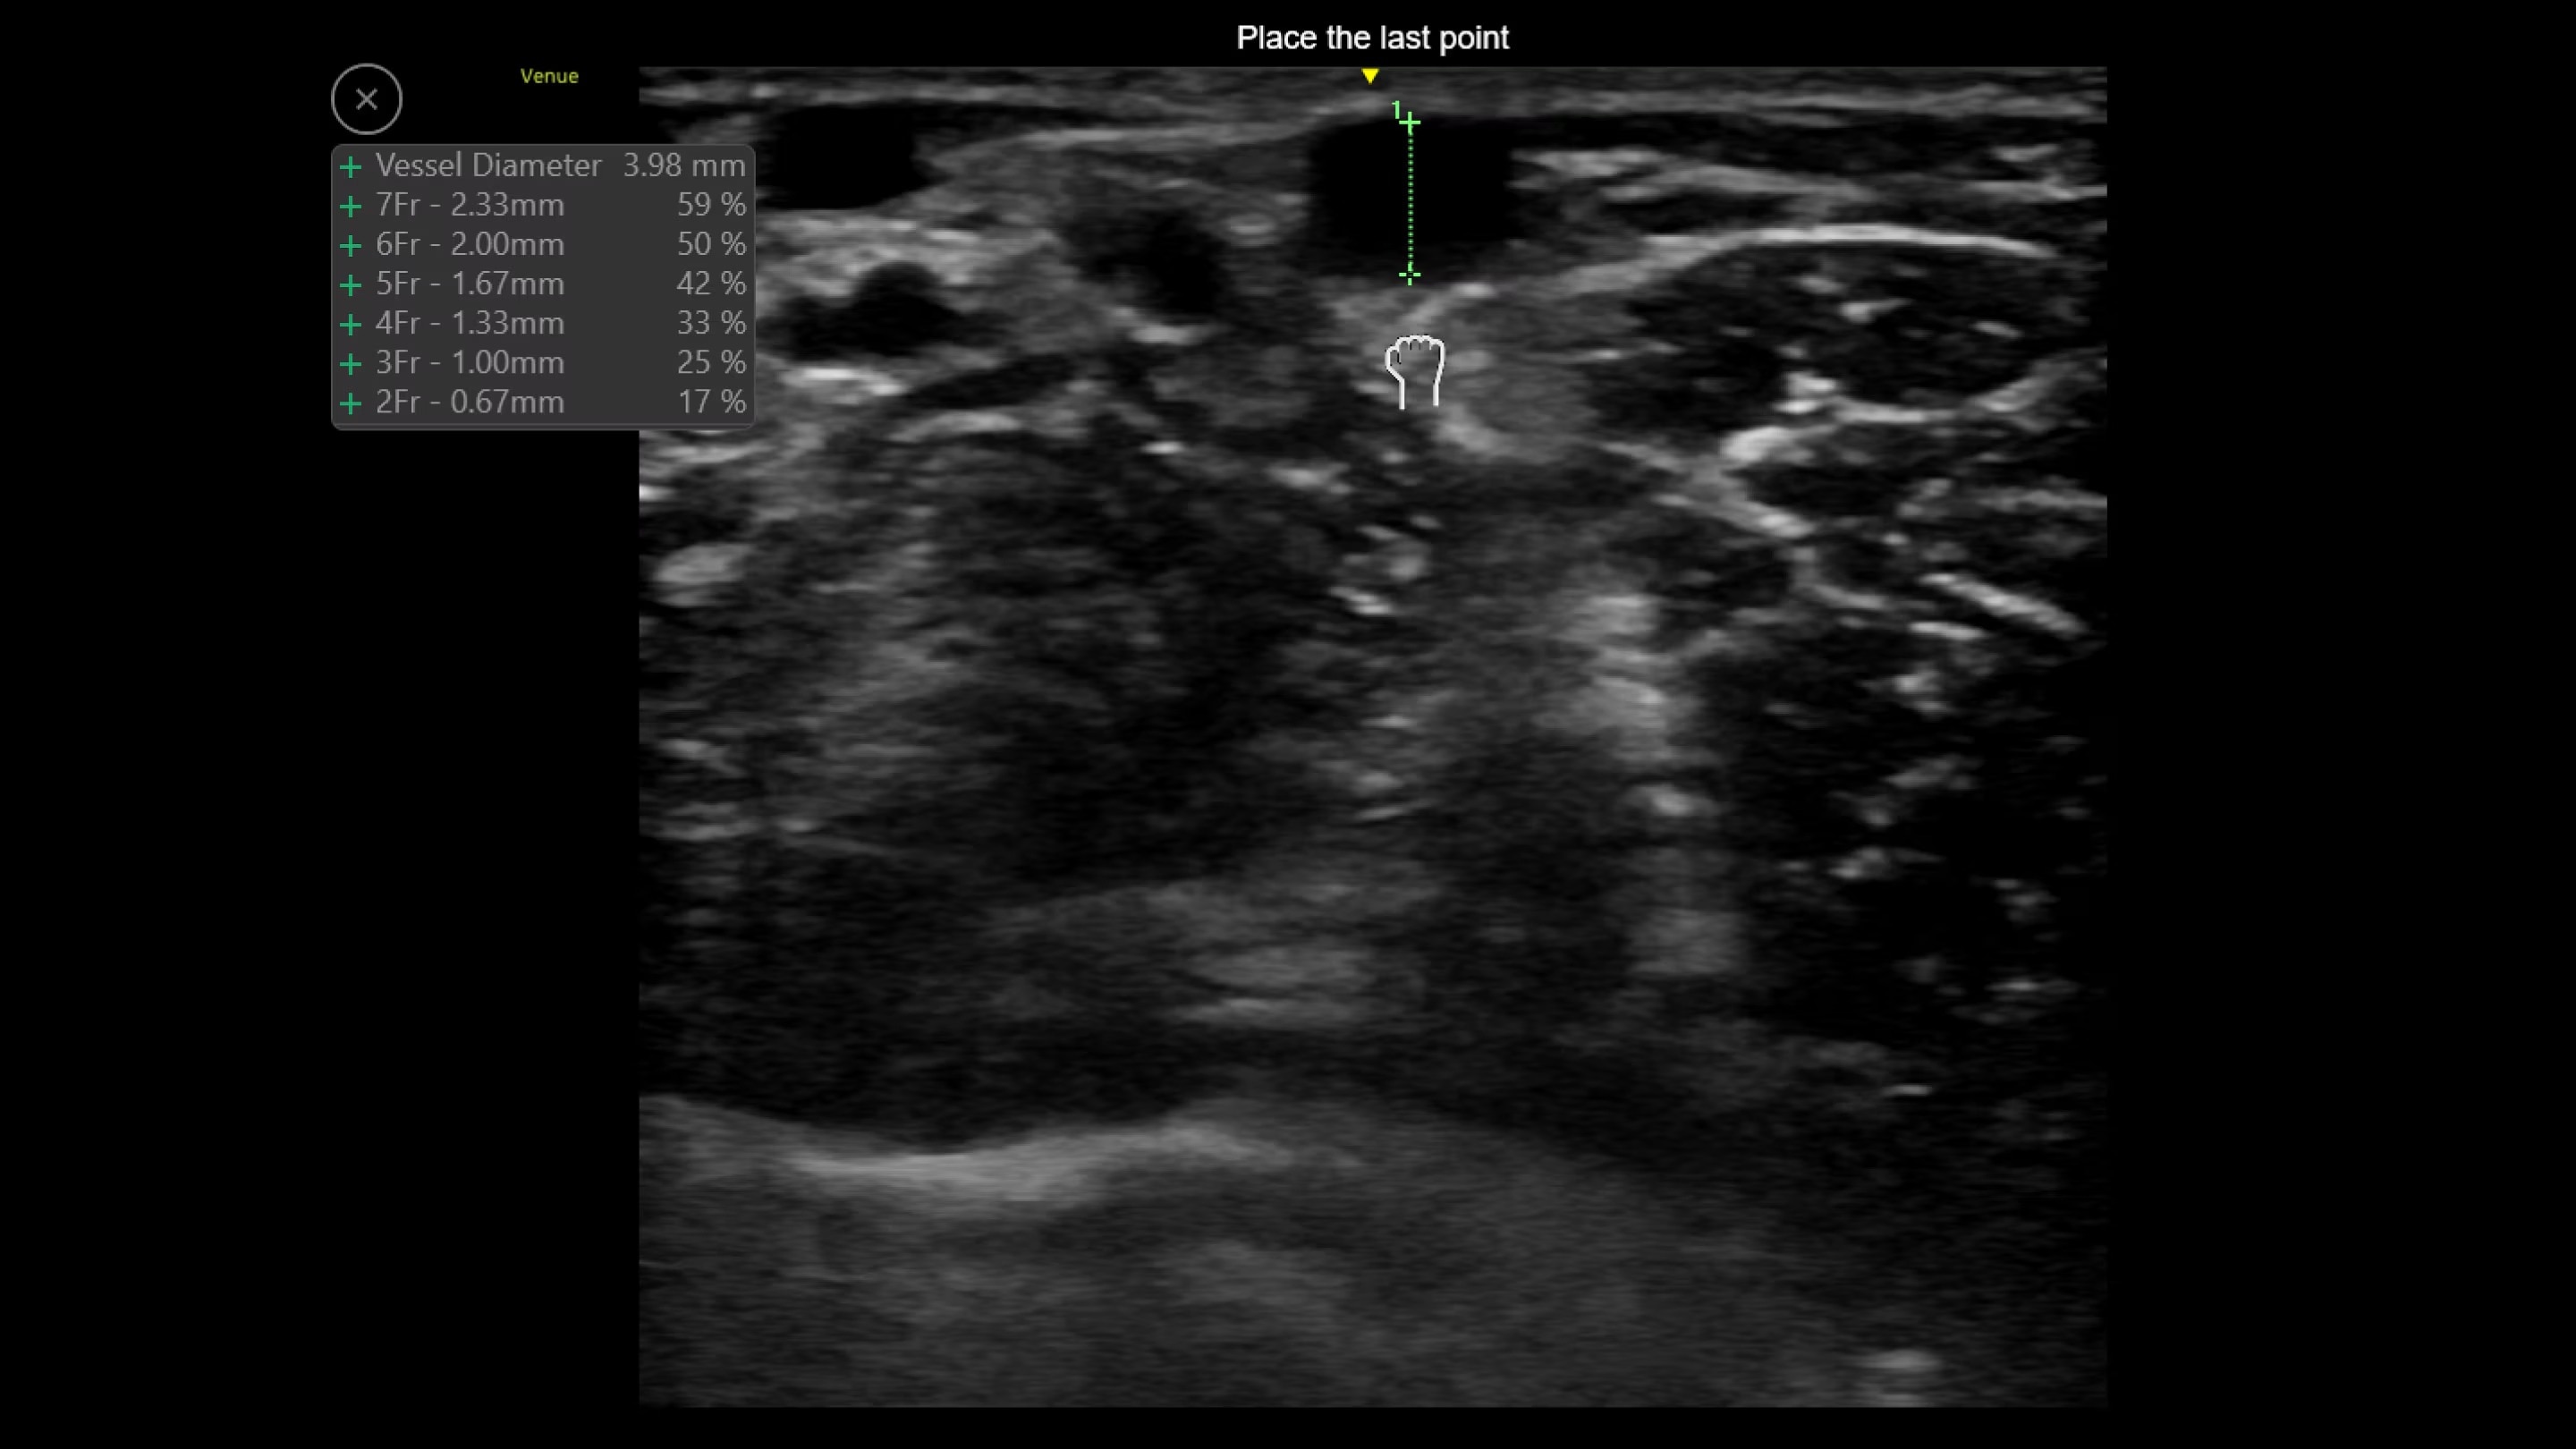

Venue probes

Experience clear images on a range of patients from adult to pediatric with the latest probes for the Venue family.